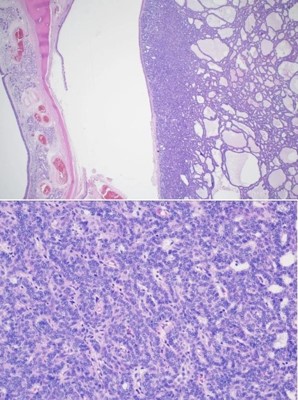

The patient was seen in an outpatient setting for a two week follow-up and discussion of final pathology results. These showed two masses: ameloblastoma with the invasion of the hard palate, posterior maxilla, and maxillary sinus (Figure 5) as well as a SCC with the cartilaginous and bony invasion of the nasal septum and nasal bone (Figure 6). During this clinic visit, he reported some discharge from one of the incisions and flap edema. He was otherwise doing well, with significant improvements in dysphagia and nasal obstruction. The flap adhered well to native tissue and appeared healthy. The infection cleared up over the next two weeks on a course of antibiotics, and the patient’s nasogastric tube was removed within the following three weeks.

We report a case of extensive nasal bone, hard palate, and sinus invasion from squamous cell carcinoma, which muddied the identification of an ameloblastoma. Simultaneous occurrences of ameloblastomas and SCC are rare, and it is difficult to appreciate both entities during initial examination. The ameloblastoma was present along the left maxillary sinus, posterior maxilla, and hard palate. Where moderately differentiated keratinizing squamous cell carcinoma was seen along the nasal bone and septal cartilage. In this case, metastatic disease was not found, and the margins were negative. The pathological staging was pT3N0M0 and pT4N0M0 for the ameloblastoma and squamous cell carcinoma, respectively. He was referred to radiation oncology and recommended to proceed with radiation therapy, but the patient opted not to pursue it. Previous case reports discuss the radiosensitivity of squamous cell carcinoma and the uncertainness of the role of radiation therapy in ameloblastomas [5,6].